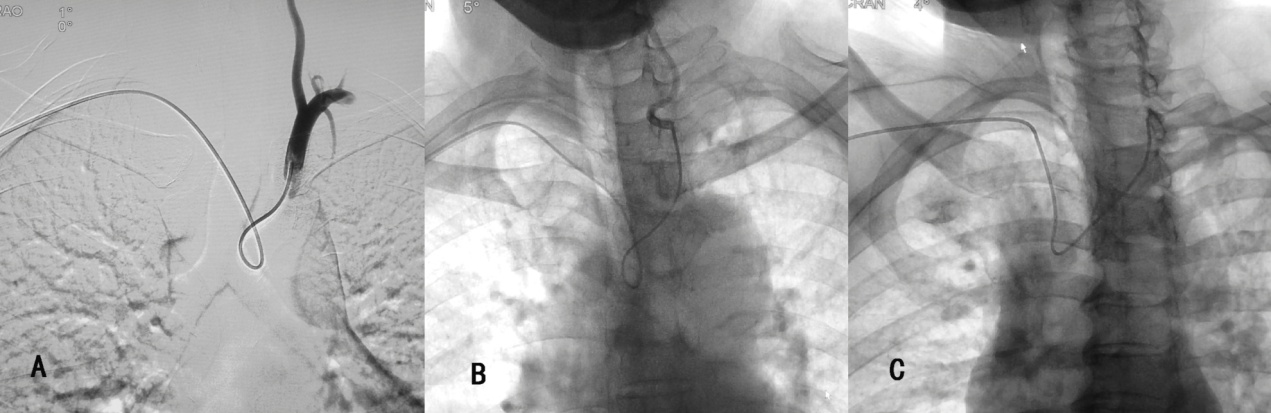

新型导管在临床使用中的表现

改良导管分别对左、右侧颈总动脉及左、右侧椎动脉的超选示意图。

我神经内科学科带头人罗宁博士已研发出新型经桡动脉全脑血管造影导管并获得国家专利,临床使用中取得很好的效果,该专利已与国内知名公司取得合作协议,很快将在临床进行推广。